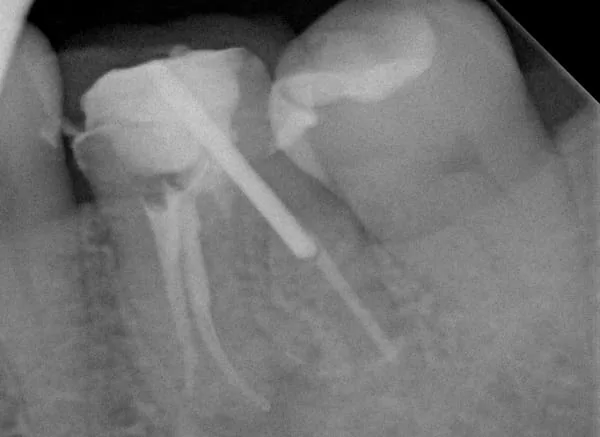

遠心的牙根並無發炎狀況,因此無須再次治療,本次治療主要針對近心的兩個牙根做顯微根管治療。

顯 微 根 管 治 療 後